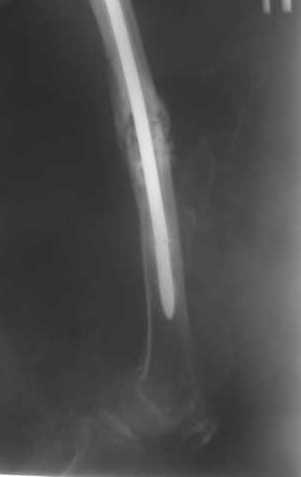

Пациенту М., 30-ти лет, 1,5 года назад в одной из московских больниц был выполнен остеосинтез бедренной кости штифтом UFN (диаметр штифта 9 мм).

К нам больной поступил с признаками ложного сустава бедренной кости, перелома

штифта и дистального блокирующего винта (images 1,2,3).

27 марта выполнено удаление блокирующих винтов (сломанный винт пришлось высверливать цапфен-бором), сломанного штифта (дистальный фрагмент удален через канал, образованный разверткой из коленного сустава - image 4),

рассверливание костно-мозгового канала, реостеосинтез штифтом UFN (при проведении штифта в дистальном отломке мы использовали поляризующий винт, диаметр штифта 10 мм). После операции в связи гемартрозом дважды (на 1 и 3 сутки) выполняли пункцию коленного сустава. Сейчас признаков скопления жидкости в полости сустава нет. Послеоперационные рентгенограммы - images 5, 6, 7.